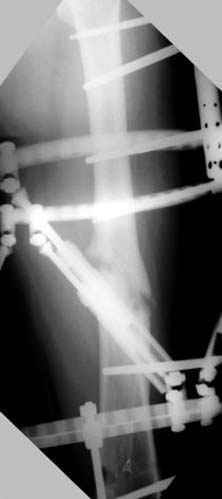

Несколько снимков из моей коллекции, чтобы разьяснить, почему мы до сих пор делаем различные варианты остеотомии.

На рисунке N1 предоперационный план лечения ложного сустава шейки бедра- линия ложного сустава, угол и направление введения импланта, клиновидная остеотомия в градусах и миллиметрах, второй снимок после коррекции, расчет, на сколько удлиняется конечность и размеры импланта;

N3 рисунок окончательный снимок, после операции моя рентгенограмма должен выглядеть примерно как эта картина. На N4 снимке клин перед удалением; N5 послеоперации 3 нед.; N6 окончательная рентгенограмма.

(доложен в Ст. Петербурге 2003 и в Москве 2004)

пластическая модель; и коррекция бедра аппаратом Илизарова.